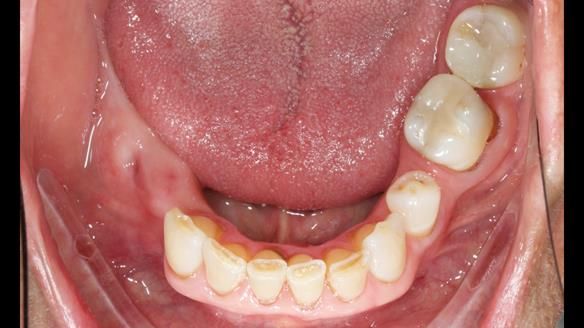

Welcome to Newsletter 61. In this edition, I walk through the process of creating and fitting a metal based lower partial denture for Joyce, a fit and healthy 76 -year-old woman.This issue shows the complete protocol workflow for achieving an exceptionally well-fitted and aesthetically good RPD.

Joyce's Case Presentation 61

Welcome to Newsletter 61. In this edition, I walk through the process of creating and fitting a metal based lower partial denture for Joyce, a fit and healthy 76 -year-old woman.

Joyce self-referred to me for specialist prosthodontics.

The missing lower right teeth to be replaced with a metal based partial denture.

The detailed clinical situation and treatment process are outlined below, with clinical work provided by me and technical work by Rowan Garstang. The treatment spanned six visits for denture fitting and one review.